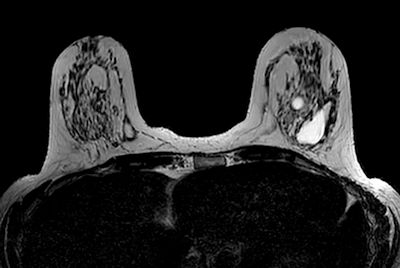

Breast 3D and 4D imaging

-